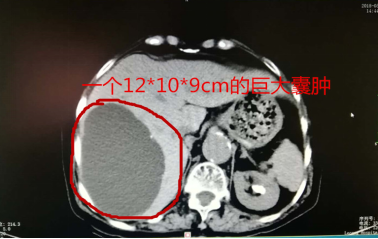

肝里有个“大芒果”!三个小孔解决老奶奶的“腹痛”烦恼!

刘奶奶近大半年在劳作时,上腹部就会出现胀痛的感觉,特别是弯腰时更为明显,这真是让人莫名其妙且苦恼!